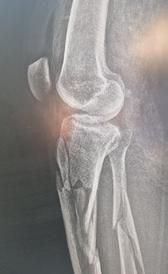

Figura 2 - Bărbat de 59 de ani, fără antecedente medicale semnificative și fără spitalizări anterioare. Pacientul a ajuns la urgențe cu durere bruscă și mobilitate redusă a șoldului drept, apărute în timp ce încerca să prindă un mijloc de transport în comun. Radiografia a arătat o fractură patologică la nivelul femurului drept (A). Investigațiile suplimentare, inclusiv analize de laborator și CT toraco-abdominopelvin, au relevat o tumoră canceroasă la rinichiul stâng. Deoarece metastaza era limitată la treimea superioară a femurului drept, s-a decis îndepărtarea chirurgicală a leziunii renale și reconstrucția femurului cu o proteză modulară (B).